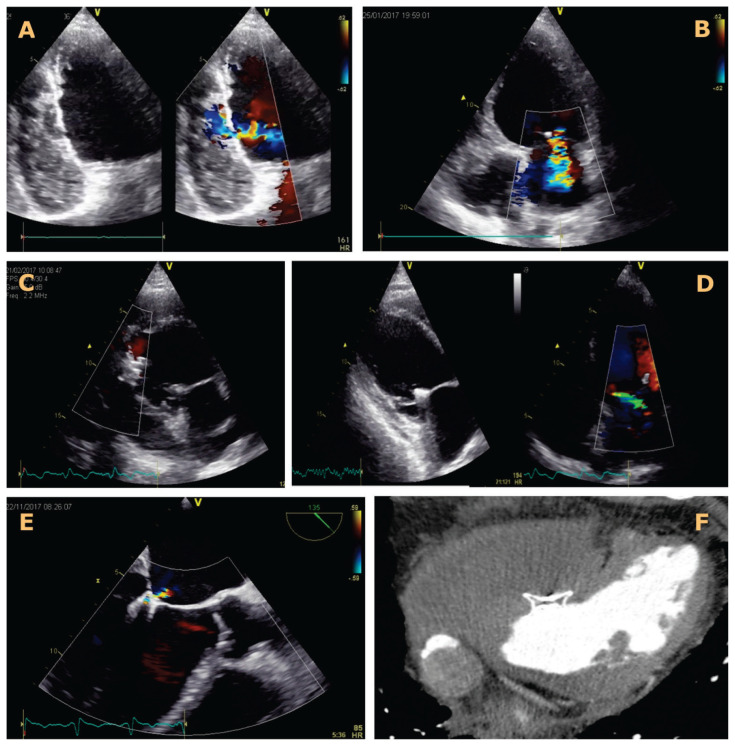

Percutaneous treatment of left ventricular free wall rupture and severe mitral regurgitation in a two-week myocardial infarction.